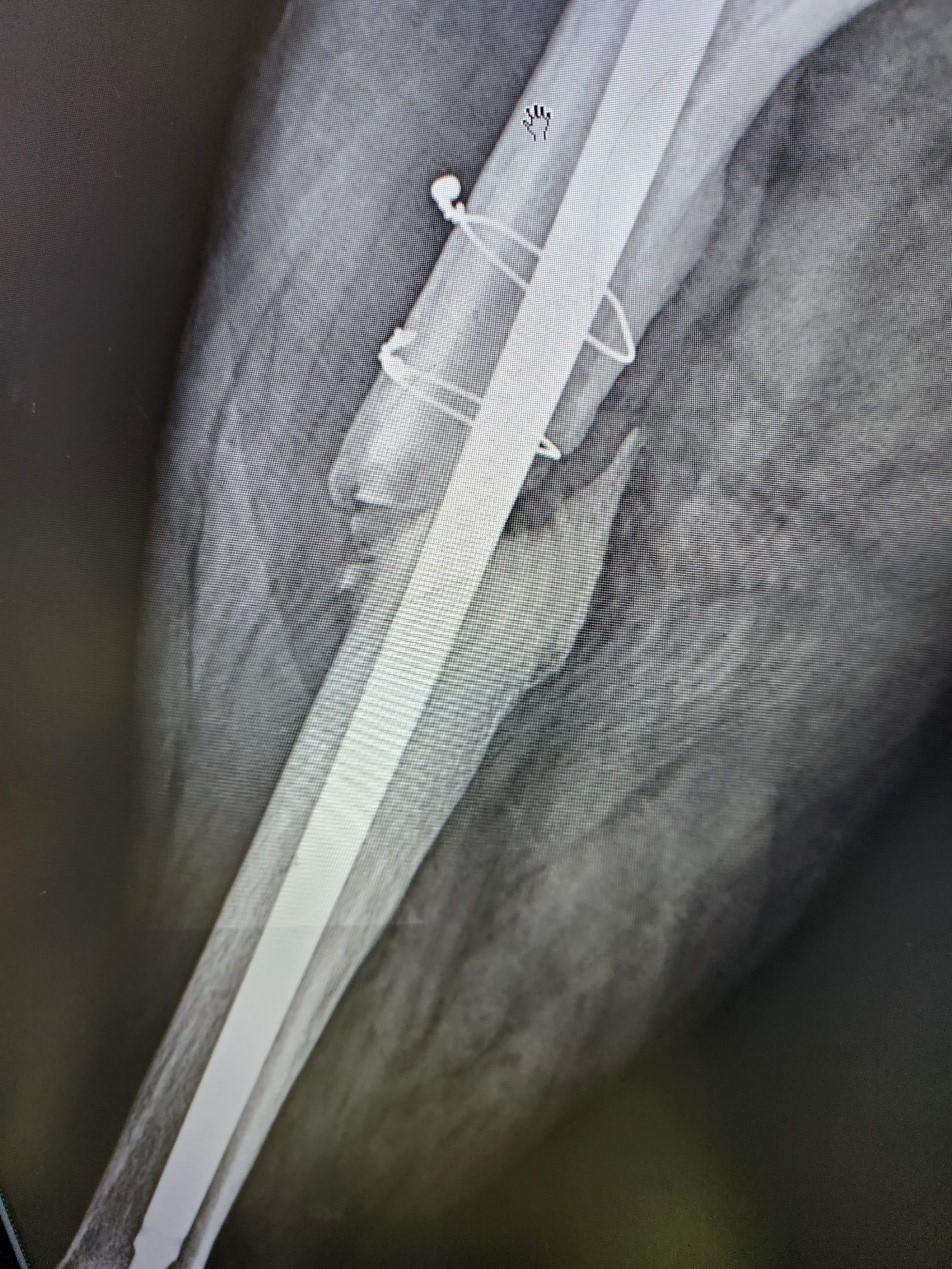

- 使用了不正確的鋼板固定:導致骨折處不穩定,進而成骨細胞生長困難而產生不會愈合。(圖1)

First, improper plate fixation causes instability and nonunion (Figure 1). In this case, even if ACS is injected, the instability will prevent the production of osteoblasts and cause bone nonunion.

(圖一) 不夠粗大的骨髓內釘產生不穩定的固定搖晃,而使骨不易生成